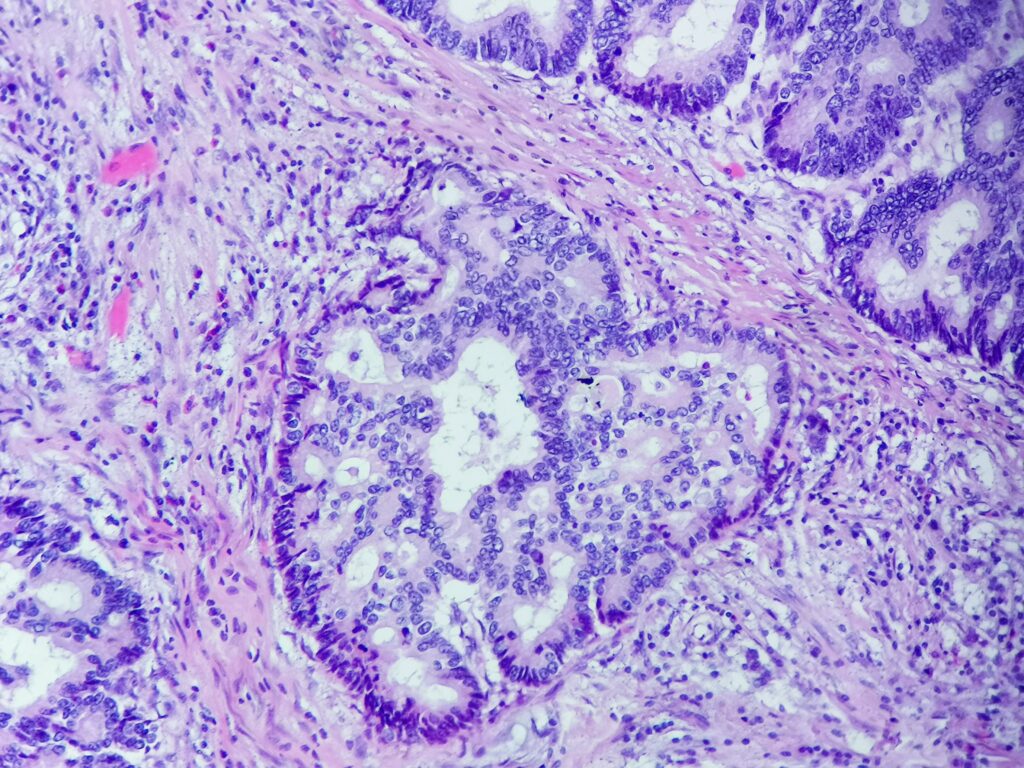

Obrazy mikroskopowe: